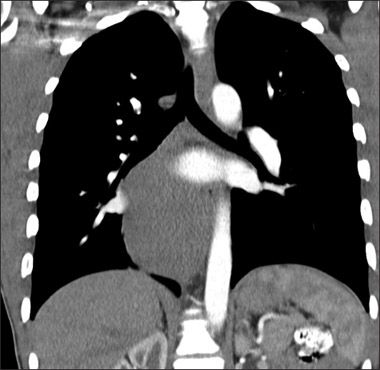

An abdominal radiographic series showed a right mediastinal soft tissue abnormality, prompting a CT scan of the chest. This showed a large 9 × 5.4 × 10-cm smoothly marginated, hypodense, homogeneous mass that emanated from the azygoesophageal recess and extended along the right aspect of the posterior mediastinum and aorta, displacing the right lower lobe of the lung and esophageal lumen. The mass was consistent with the diagnosis of a bronchogenic cyst-with esophageal duplication cyst, neuroenteric cyst, lymphangioma, and pericardial cyst included in the differential.